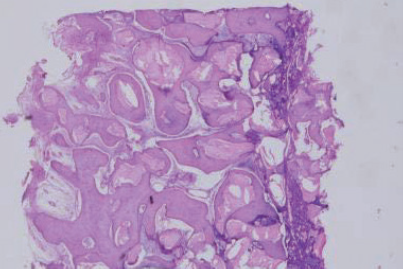

GBR and suture with granulation tissue

Re- entry surgery after 7 month

H&E Staining